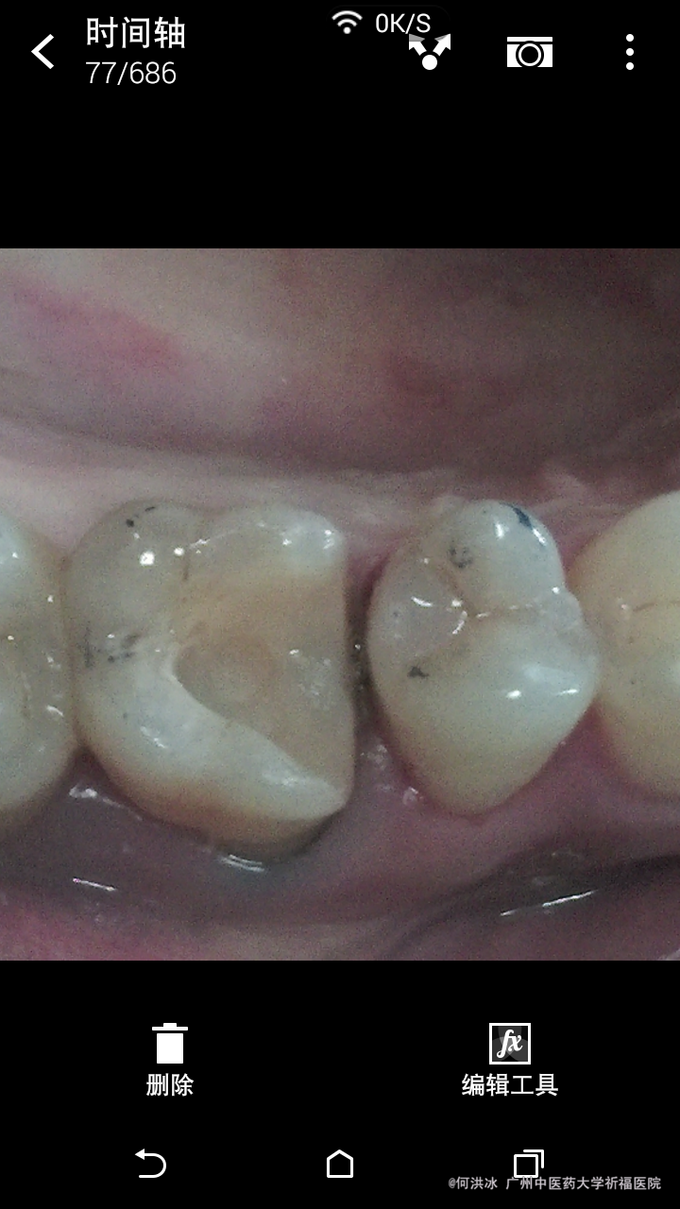

根据检查结果,提示,如冠修复,势必磨牙组织太多,更可怕的是,几乎全部釉质等坚硬组织可能去掉,这样基牙的抗力大大削弱。同时依据患者的要求,决定选用瓷嵌体修复。铸瓷价格偏高,病患没选择。 处理步骤: 1,牙周软组织准备,这一定要放在首位。去除结石,控制炎症。特别是判断生物学高度。避免后期的并发症。 2,硬组织准备:去尽腐质,薄壁弱尖,无基釉等。 3,寻找固位形,根管内,箱状等。 4,龈壁处理,这是最关键的部位,必要时使用“深部边缘提升”(Deep Margin Elevation,DME)。 5,垫底,填倒凹,结合流体树脂和通用树脂。 6,比色。本病例,因原牙体组织微发暗,色调不是太理想。 7,取精密印模。 7,试戴和粘固。

临床诊断不是太难。个人认为最关键的地方在以下几点: 1,牙周处理及生物学宽度考量。 2,硬组织的去除和保留。 3,比色有点难度。 4,粘接剂的选择。咱选用3M的小蜜蜂。当然用Varilink II最好。